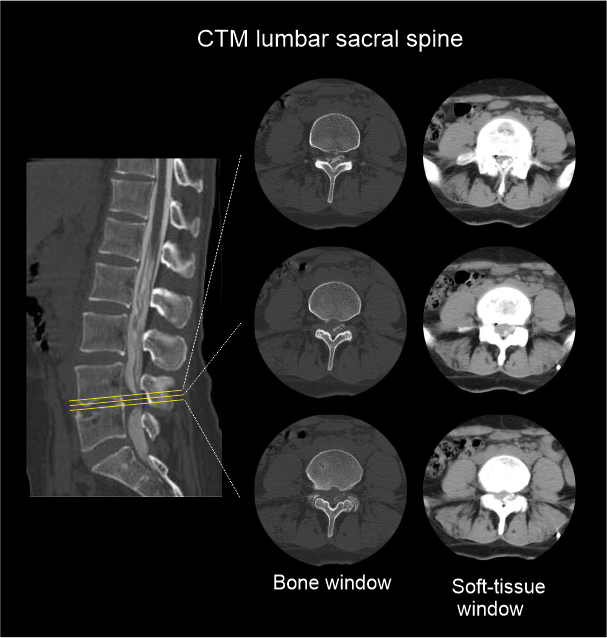

- Sagittal and coronal images with ≤ 2 mm slice thickness in bone window (WW: 3500, WL: 350).

- Contagious axial slices in bone window and soft-tissue window (WW:500, WL:50) with ≤ 2mm and ≤ 3mm slice thicknesses respectively.

- Axial images through inter-vertebral disk for the assessment of spinal cord compressions.